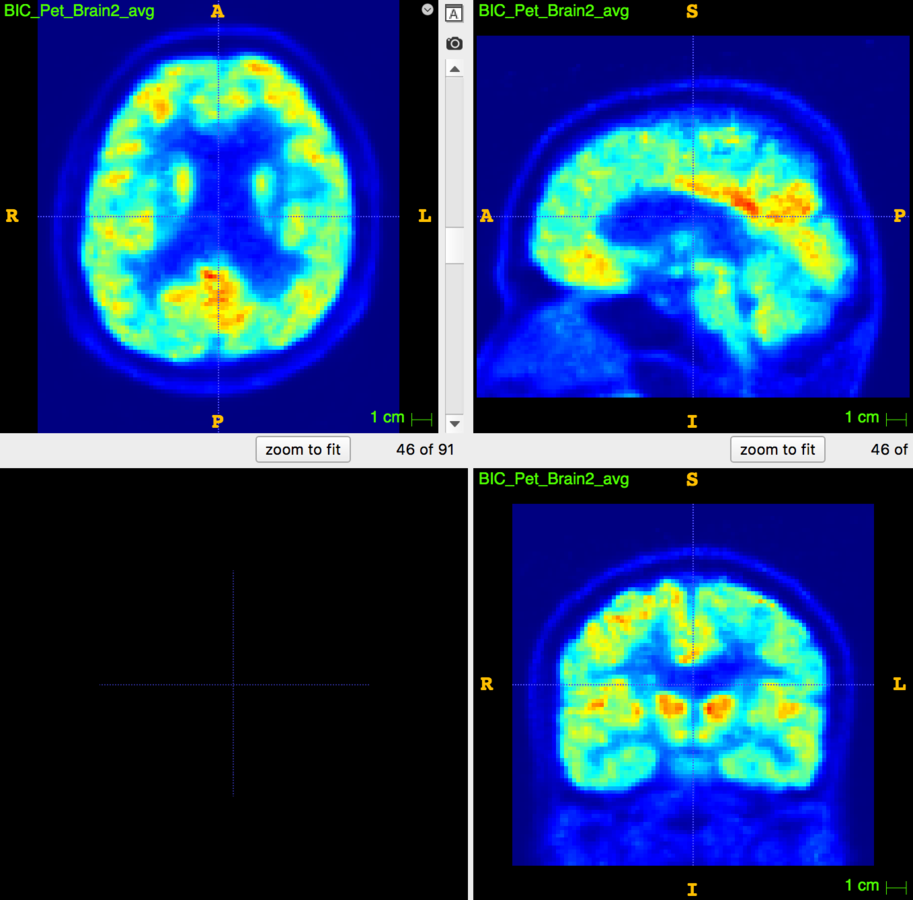

4. Glucose PET/MRI in MS

29 patients, 14 CIS/eRRMS and 15 RRMS underwent a PET/MRI with:

- MRI sequences: 3D T1, 3D FLAIR, 3D DIR

- 18Fdg PET in list-mode

The aim is to study the relationship between:

- Cortical Thickness

- WM/GM lesion number/volume

- aMRGlu

Results are hard to put together!

No correlation was demonstrated between CTh and WM and GM lesion load

No correlation was found between global and regional aMRglu and CTh.

aMRglu correlated with lesion load

Inverse correlation was found between:

- the total number of focal lesions (WM+GM lesions) and the global cortical aMRglu (R=-0.36 e p=0.04)

- WM lesion volume and number and cortical global aMRglu (R=-0.4 and p=0.02 for both)

-

GM lesion number with global aMRglu (R=-0.36, p=0.046)